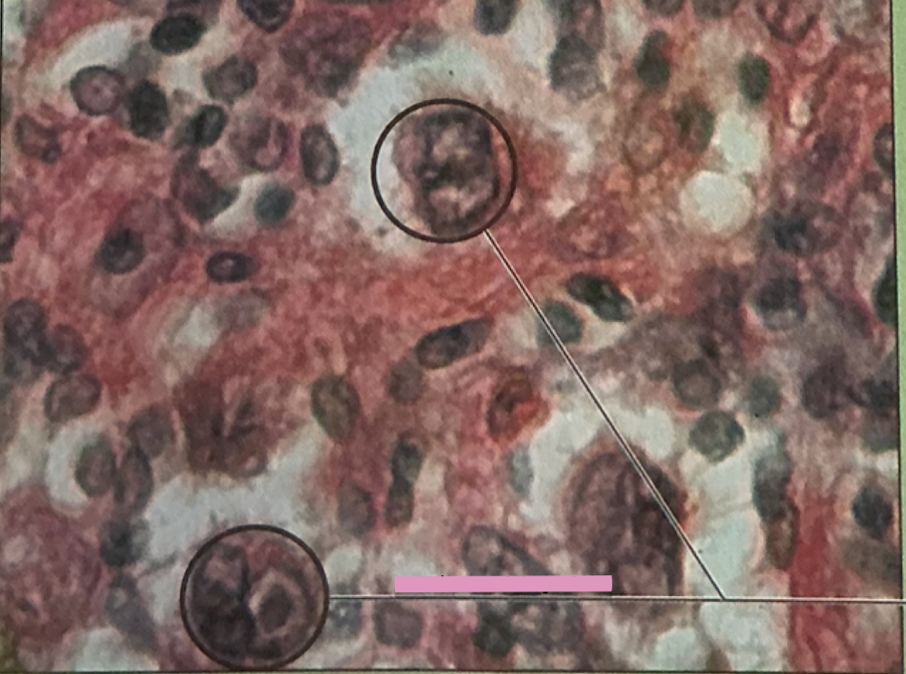

reed-sternberg cells

derived from B lymphocytes